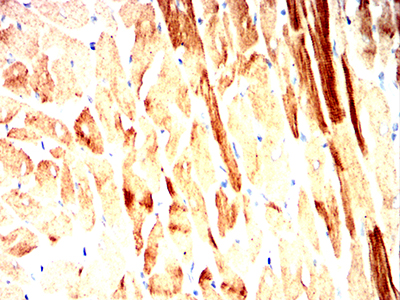

Immunohistochemical analysis of paraffin-embedded Mouse Heart using SQSTM1 mouse mAb with DAB staining.

-

Immunohistochemical analysis of paraffin-embedded Rat Heart using SQSTM1 mouse mAb with DAB staining.

Immunohistochemical analysis of paraffin-embedded Rabbit Heart using SQSTM1 mouse mAb with DAB staining.